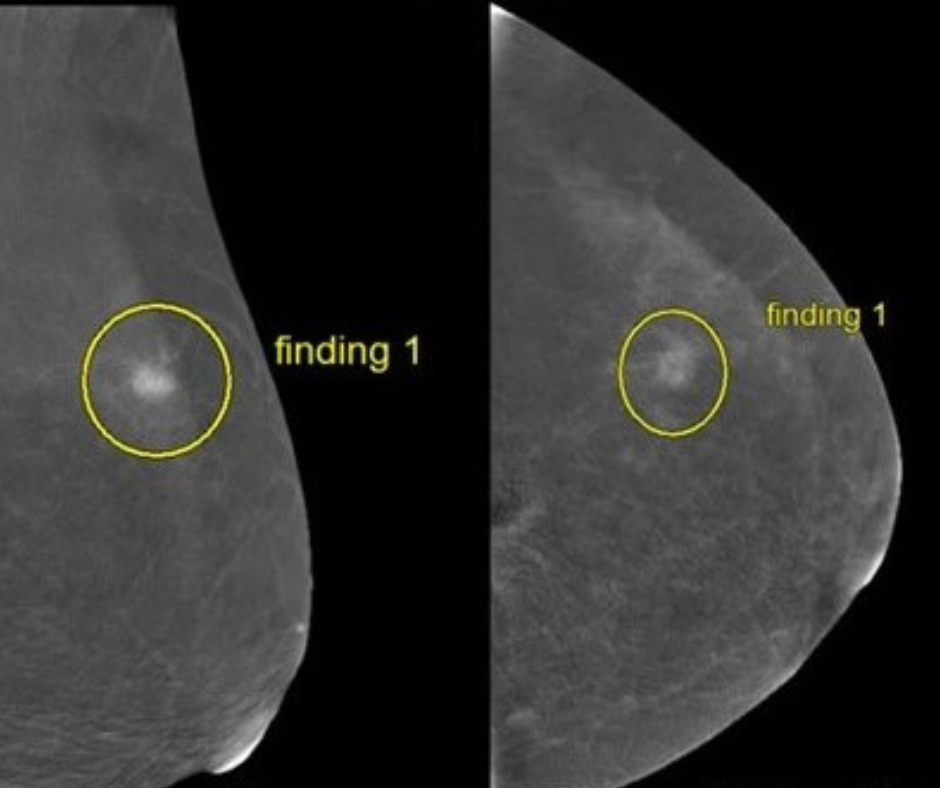

Researchers found that ChatGPT offered appropriate responses to 22 out of 25 patient-oriented questions on mammography screening, dense breasts, BI-RADS scoring and other topics related to breast cancer screening and prevention.